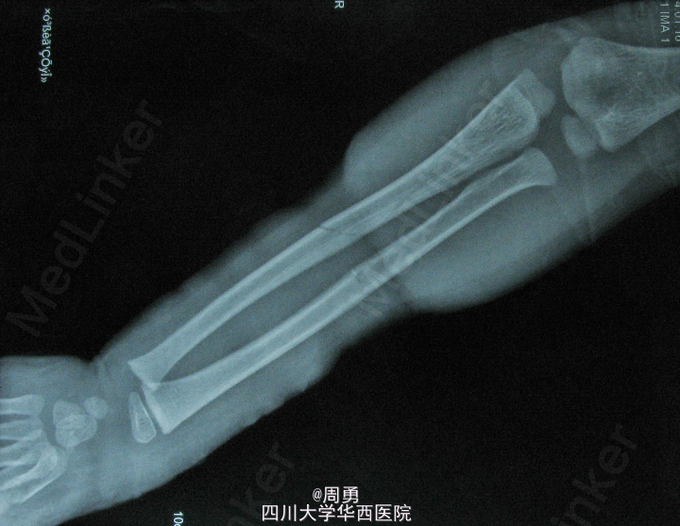

6岁,藏族男性,因“摔伤致左前臂疼痛3+天,加重伴发黑、功能障碍3天”来院就诊。 诊断:左前臂中上1/3以远坏死。 处理:截肢。 追问病史:患者系简单摔伤,无伤口,伤后由当地藏医处理,诉予以布带加压捆扎(纯布带,无夹板等,具体治疗方法不详),捆扎之后有不适,当地藏医告知正常反应,患者家属带患者离开,第二天拆除布带才发现出了问题,来华西时已无力回天。 失误:片子上可见为简单闭合青枝骨折,只需石膏或夹板固定即可,甚至单纯采用三角巾悬吊并制动即可,而当地藏医毫无道理的加压捆扎,导致肢体缺血;患者诉捆扎不适时尚有回头之路,可惜却酿成恶果!患者家属诉当地藏医为老游医,经验丰富,听闻顿感毛骨悚然,还不知有多少惨剧已上演或将上演!已告诉患者家属回去追责,不知道悲恸的家属能否阻止惨剧再发生。 教训:临床上加压包扎应用非常广泛,但因加压包扎压力过大产生不良后果的案例也不在少数!许多医生对加压包扎这一”简单“操作不以为然,最终铸成大错!时刻警示自己:加压前要综合判断,加压时要细致谨慎,既保证压力足够,又保证不影响神经和血循,加压后要再次检查松紧度,并告知宣教患者不适立即复诊,尤其骨折行石膏固定患者,常因骨折48小时内水肿高峰变相导致加压过紧!特殊加压,如止血等,切记定时松开!总之,态度决定一切,细节决定成败!